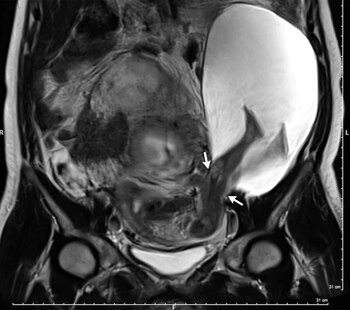

Lo que halló durante una consulta de rutina de una mujer embarazada de 22 semanas fue algo extremadamente inusual. Durante el estudio ecográfico que le realizó, pudo observar cómo dos piernas sobresalían por el costado de su útero. Eran las extremidades del bebé que estaba gestando. Las paredes de su órgano se habían roto. Era el caso número 27 registrado en la historia de la medicina.

Según Bouet, como consecuencia de sus cinco cesáreas previas, las paredes de su útero habían desarrollado una rigidez mayor de la que suele verse en los embarazos. La pared se rompió cuando fue imposible que continuara expandiéndose. Afortunadamente para la mujer, las piernas del su bebé actuaron como tapones, impidiendo una hemorragia que hubiera resultado letal para ambos.